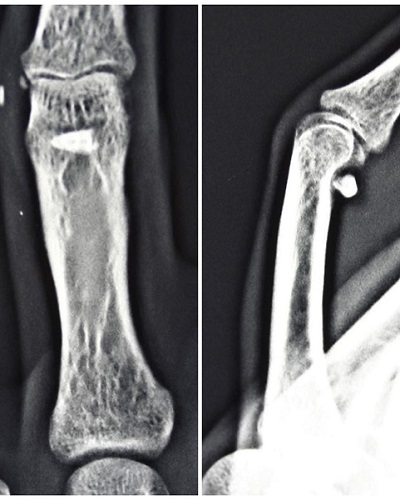

Затем палец стал плохо гнуться. На рентгене врачи увидели инородное дело, но в ходе операции не нашли его. В итоге красноярка решила обратиться в краевую больницу. Врач Вадим Кеосьян немало удивился увиденному – зуб находился под сухожилиями и ладонной связкой сустава.

«Кроме удаления зуба, пришлось отсечь ладонную связку сустава и насильно его разогнуть, а также сделать Z-пластику рубца, чтобы он не стягивал палец», - рассказал медик.

Также на неделю наложили лангету, чтобы поддерживать разгибание пальца.